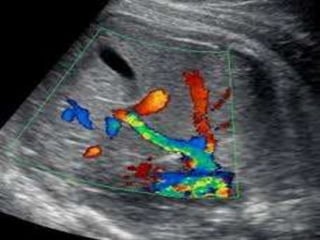

Ultrasound imaging and insonation

• A Sagittal anterior insonation offers the best

visualization of the Ductus venosus .

• An oblique transverse section may be more

convenient and easier to obtain in some fetal

position but rarely offers visualization of the

entire length of the vessel.

• Color Doppler is an indispensable tool to

identify the high velocity flow at the isthmus

of the ductus venosus.